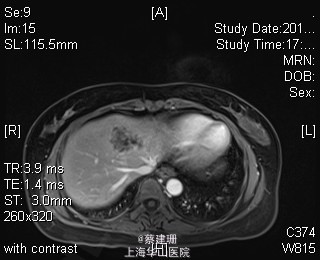

主诉:平滑肌肉瘤、肝转移癌术后,发现肝多发转移2月余。 现病史:患者3年前外院检查发现后腹膜肿瘤,外院行后腹膜肿瘤切除术后,术后病理为:平滑肌肉瘤,2013年12发现肝左叶转移癌,外院行肝左叶肿瘤切除术,术后病理为:梭行平滑肌肉瘤。2月余前患者复查发现肝脏多发转移,2015-4月肝脏MRI:肝脏多发转移。现患者无恶心、呕吐,无呕血、黑便,无皮肤巩膜黄染,无剧烈腹痛发作。现为进一步诊治收住入院。

查体:锁骨上淋巴结未扪及肿大;腹部平坦,可见陈旧性手术疤痕。未见肠型、胃型蠕动波,腹软,无压痛及反跳痛,无肌卫,肝脾肋下未及。Murphy’s 征(-),肝区叩击痛(-),肾区叩击痛(-);移动性浊音阴性。 辅查:2015-4月肝脏MRI:肝脏多发转移。

诊断 :1、多发肝转移癌 2、后腹膜平滑肌肉瘤术后 3、肝转移癌术后 处理:取右侧肋缘下切口,左侧延长,逐层切开进腹,探查腹腔:见上腹部粘连,仔细游离上腹部腹腔粘连,探查见无腹水,胃、肠、胰、脾及盆腔脏器未及异常,腹腔未见明显转移结节;肝脏无硬化。肝门淋巴结无肿大,门静脉主干无栓子。肿瘤多枚,最大两枚位于肝右叶VI段,肿瘤大小约7*6*5cm。V段肿瘤直径约5cm。左内叶肿瘤多枚,直径0.5-4cm,紧贴第一肝门。左外叶肿瘤多枚,直径1-3cm,肿块质韧,边界尚清,有包膜。术中诊断为转移性肝癌,决定行左半肝切除,肝右叶特殊肝段切除。